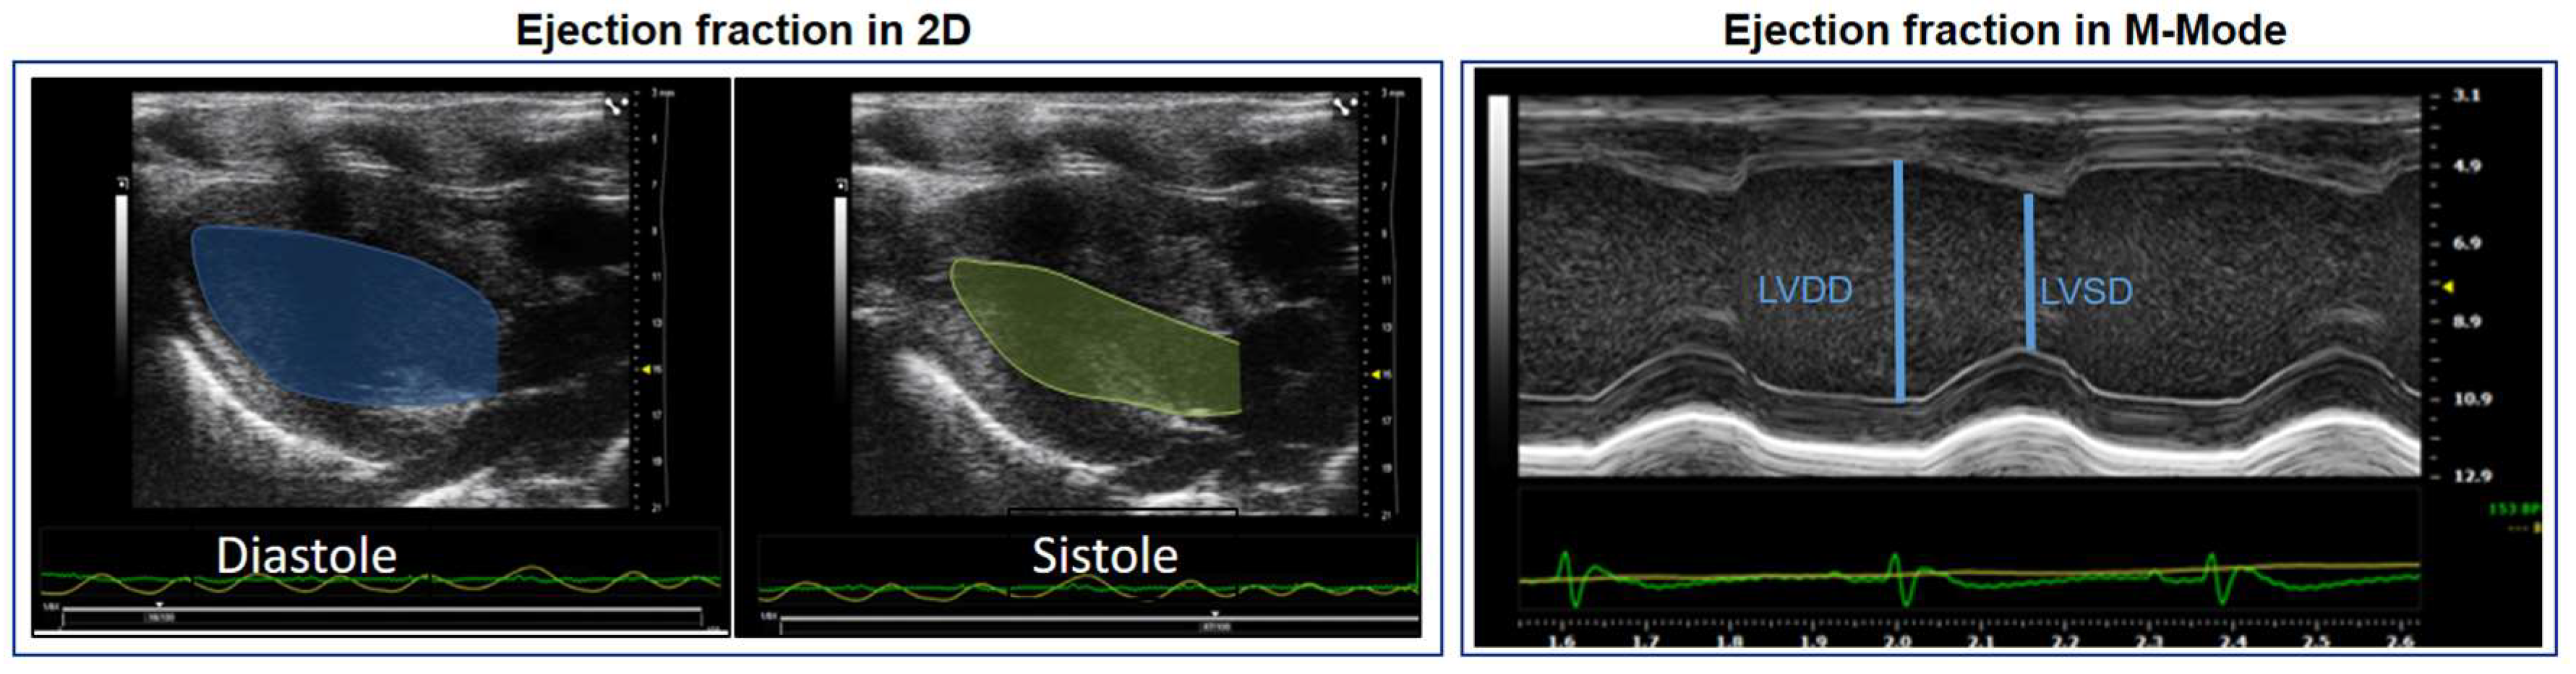

7. Conventional Assessment of LVEF in Rodent Models